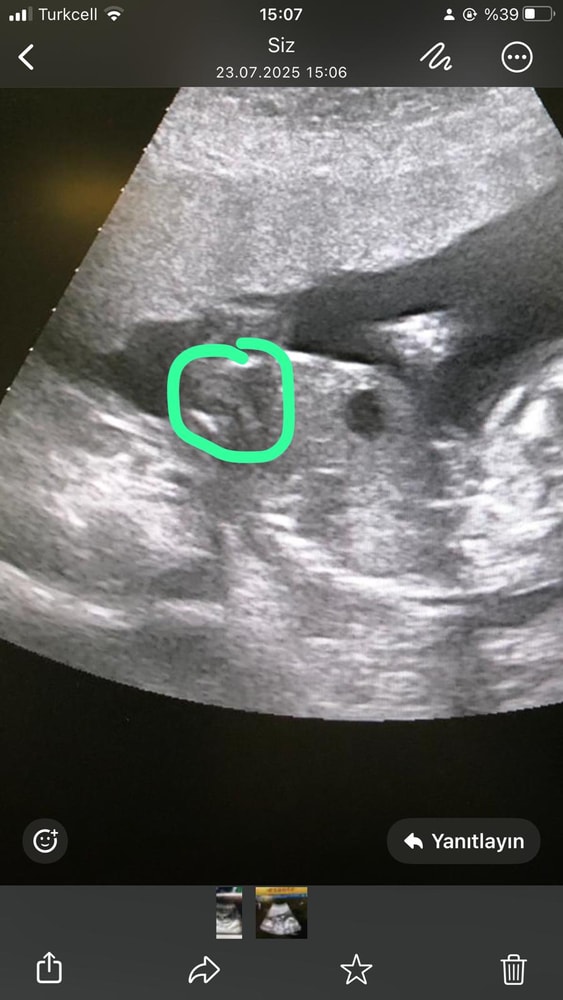

Севда в Благополучная беременность 5 месяцев Это УЗИ моей сестры Всё о родах (ЕР, КС, вопросы о родоразрешении) Срок 18 УЗИ не сказала точный полКто разбирается Посмотрите еще 20 записей на эту тему Отменить Ответить Марина По-моему и итак все видно. 23.07.2025 Ответить Оксана Очень похож на мальчика 23.07.2025 Ответить Севда Оксана, мне тоже так показалось но незнаю 23.07.2025 Ответить Оксана Севда, прям почти уверенна ) 23.07.2025 Ответить Шейка 35, 38+1 39 неделя, ложные схватки. Чаты Беременных Выберите чат: Январята-2026 Февралята-2026 Мартята-2026 Апрелята-2026 Майчата-2026 Июнята-2026 Июлята-2026 Августята-2026